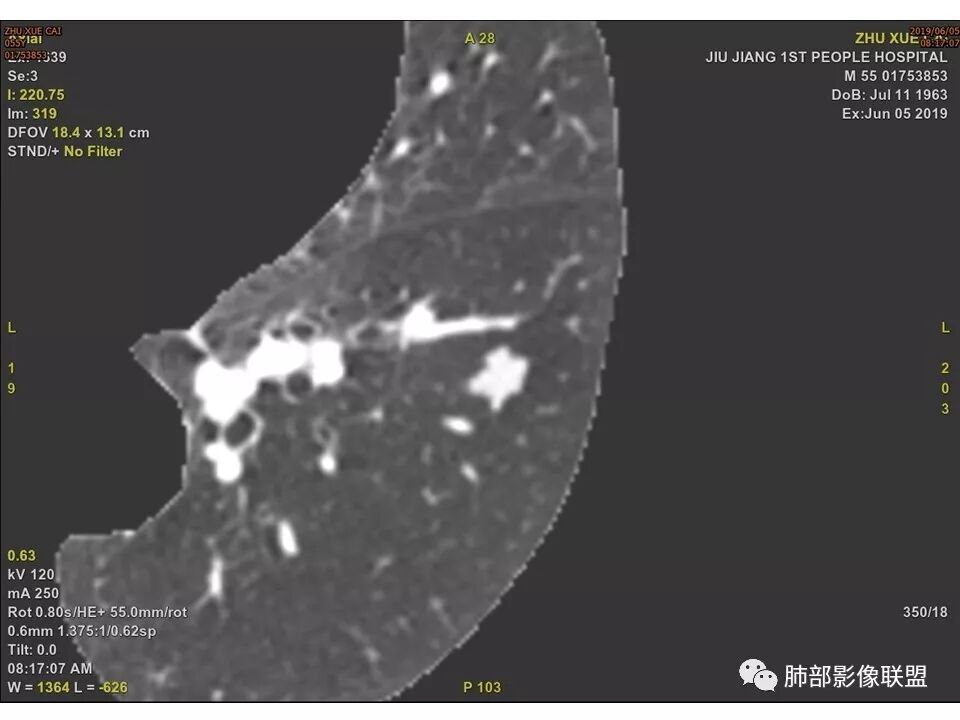

边缘有光滑,有圈黑晕,强化弱,似乎有脂肪密度,支气管截断的部位很自然,没有鼠尾状狭窄,考虑软骨型错构瘤?

这个支气管开口位置,如果是肿瘤应该有管壁浸润,也应该有膨胀感,这个没有,不像恶性肿瘤的支气管截断

病灶部分平直丶内收,有脂肪密度,不强化支持错构瘤。部分病灶有结节堆积感,分叶,与支气管、肺动脉关系密切,需鉴别腺癌。不强化进一步结核结节。

左肺下叶前基底段结节,病灶边缘分叶,边缘平直,u型征,可见气管截断,增强可见病灶边缘血管,平扫ct值低,轻度强化。考虑良性病变。

晨读病例,强化值小于20,还是提示良性,感觉支气管截断是坑,所以考虑错构瘤?肺癌待排

边缘平直,主要强化值小于20,说明基本不强化,提示良性

也咨询了病理科老师,肺软骨瘤来源于支气管透明软骨,理论上可以从黏膜下,突向支气管腔内生长,对支气管造成压迫性的阻塞。影像上和软骨瘤样错构瘤没法区分

典型CT特征包括:(1)圆形或椭圆形边界清楚的病灶。(2)大小1~4cm,有轻微分叶改变。(3)较均匀的软组织影,多伴有钙化。(4)无毛刺,卫星灶及肺门或纵隔淋巴结肿大。(5)CT增强扫描无强化或轻度强化,其强化可能与软骨瘤间质中的薄壁血管或周围慢性炎症反应有关。

鉴别诊断,主要是错构瘤。错构瘤是肺内最常见的良性肿瘤。错构瘤内常见“爆米花”样钙化,而软骨瘤钙化则多呈点状或环状钙化。病灶内脂肪密度影是错构瘤的特异性征象,而软骨瘤内无脂肪成分。此外尚需要与肉芽肿性炎、硬化性肺细胞瘤、肺癌、转移等鉴别。